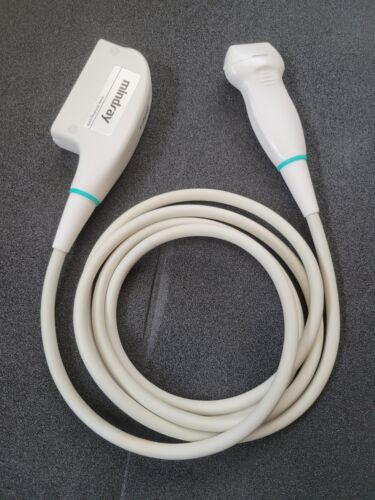

Mindray L14-6s Linear Ultrasound Transducer

Regular price $199.00 USDRegular priceUnit price / per -

Mindray L14-6s Linear Ultrasound Transducer

Regular price $999.00 USDRegular priceUnit price / per -

Mindray L14-6s Linear Ultrasound Transducer

Regular price $1,799.00 USDRegular priceUnit price / per -